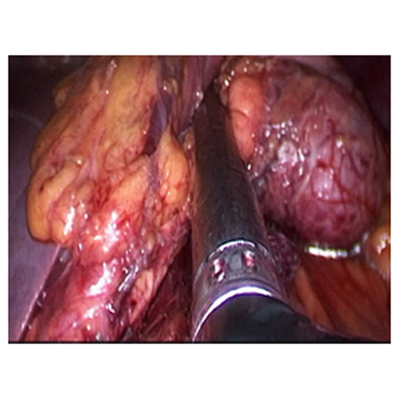

SURGERY FOR LIVER CANCER

LAPAROSCOPIC SURGERY FOR PANCREATIC TUMOUR